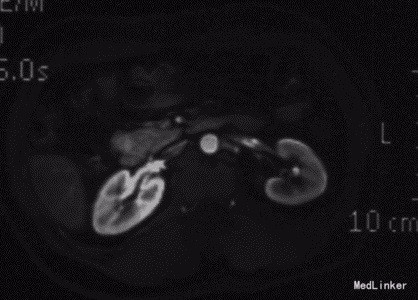

查体:神清,腹软,未及包块,无压痛及反跳痛,神经系统检查未见异常 辅查:外院头颅CT平扫:腔隙性脑梗;胰腺CT平扫:胰头、十二指肠降部稍低密度影,肝内多发小囊肿;上腹部增强CT:胰腺低密度影,考虑良性;肝内多发小囊肿。 入院检查:血、尿、粪常规、肝肾功能、电解质、凝血功能正常;AFP、CEA、CA19-9、CA125、CA15-3、CA72-4均正常;胰岛素78.33mIU/L,C肽 4.91ug/L。腹腔动脉DSA:胰头区富血供肿瘤; 胰腺增强MRI:1、胰头部富血供病变,考虑胰岛素瘤可能性大;2、肝内多发小囊肿。